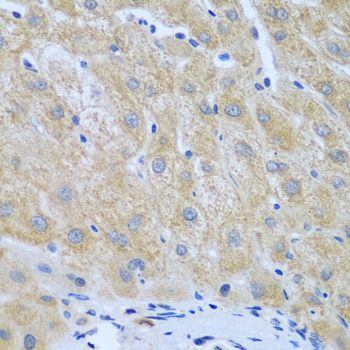

Immunohistochemistry of paraffin-embedded human liver cancer using FURIN at dilution of 1:100 (40x lens).